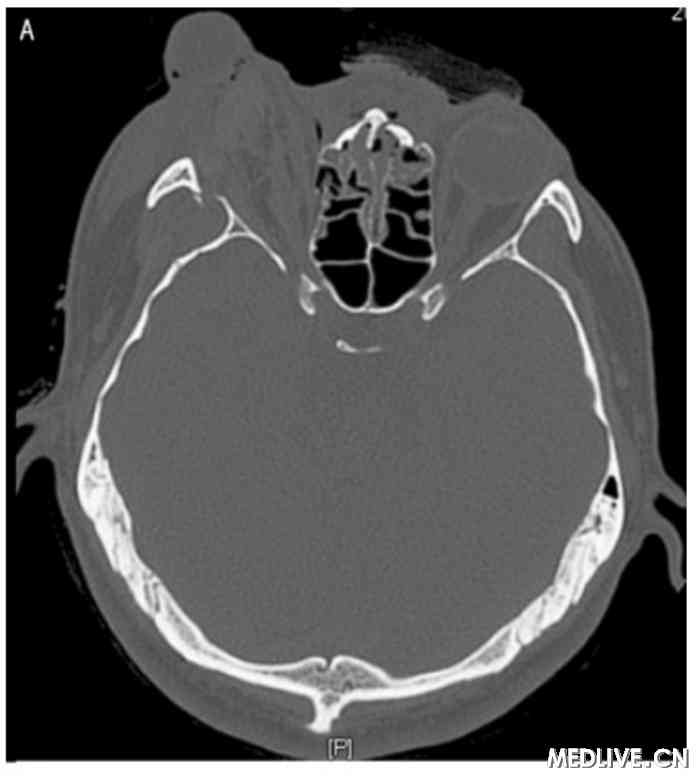

双眶三维CT 右侧眼球外突双眶三维CT 右眼眶下壁骨折

图2 双眶三维CT

A:右眼球外突,考虑存在右眼肌群及视神经损伤。右侧玻璃体内稍高密度影,出血可能性大。双侧上颌窦、筛窦、蝶窦及右侧额窦内积液;

B:右眼眶下壁骨折。